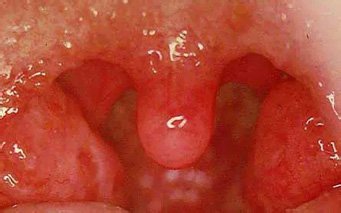

Как уже было сказано, симптомы ангины весьма яркие. По этой причине врачу не требуется назначать своему взволнованному пациенту множество диагностических процедур. Зачастую для того, чтобы констатировать болезнь горла, достаточно визуального осмотра. При осмотре врач может даже установить вид ангины, поскольку на горле будут присутствовать или отсутствовать фолликулы с гноем. Если они есть, значит, ангина гнойная, если нет – катаральная.

Основные симптомы катаральной ангины включают боль в горле, покраснение и отек миндалин, а также общее недомогание. Пациенты могут также испытывать повышенную температуру, головную боль и затрудненное глотание.